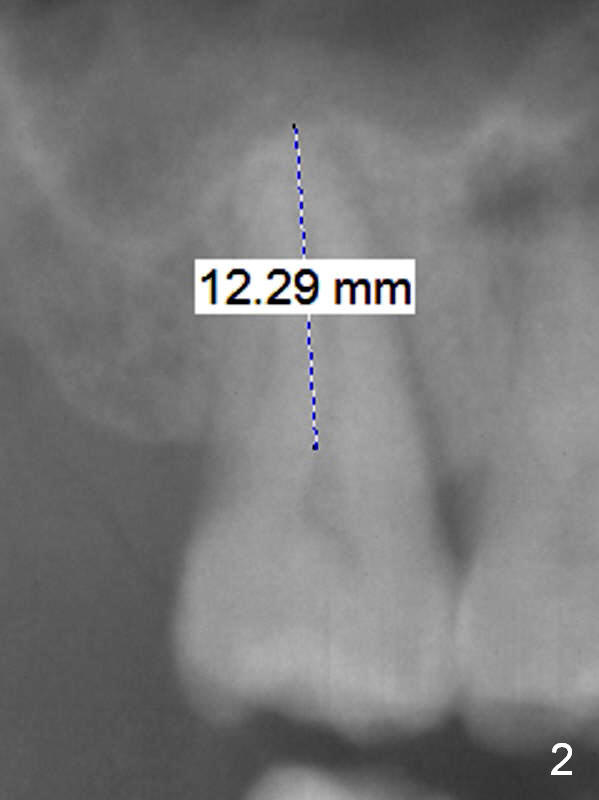

Implant Is Inserted into Socket for Stability

A 53-year-old man agrees implant treatment for crack tooth #2 (Fig.1). Since the apex overlaps the sinus floor (Fig.2 panoramic X-ray), the primary stability will be derived from tight contact of an implant with the socket. After extraction (Metronidazole), osteotomes are going to be used to break through the sinus floor (RT2-4), followed by tap drills (4.5 mm or larger (Fig.3) until achieving 35 Ncm). The implant will be one size larger. Prepare regular and extra wide surgical kits. Before implant placement, insert PRF plug and allograft/Osteogen.